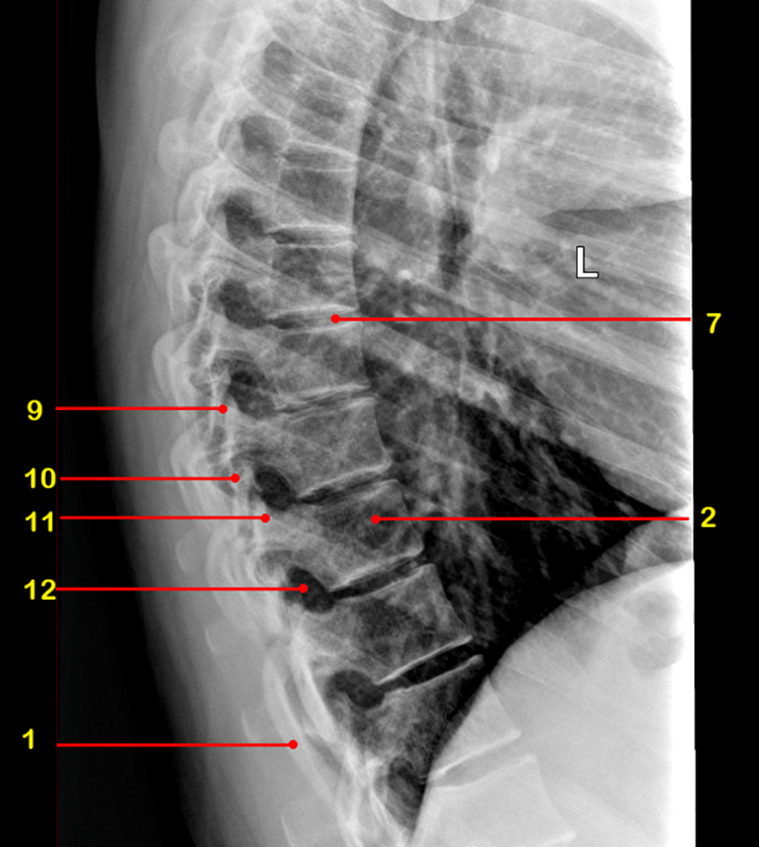

What view is this

sagittal MRI

axial

coronal